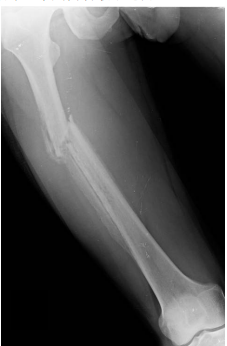

56 一位 38 歲男性主訴右膝劇烈疼痛,他約有一個月右膝疼痛病史,經國術館推拿後發現無法負重行走。 求診時發現局部腫脹,明顯壓痛及合併有輾軋聲(crepitus sound)。X 光攝影在右股骨近端有一病灶 如下圖。對此病患的診斷及治療,下列何者最不適當?

(A)實施骨骼牽引,以保持骨骼相對位置 (B)安排全身骨掃描(bone scan) (C)安排磁振造影(MRI) (D)立即進行骨折復位及內固定